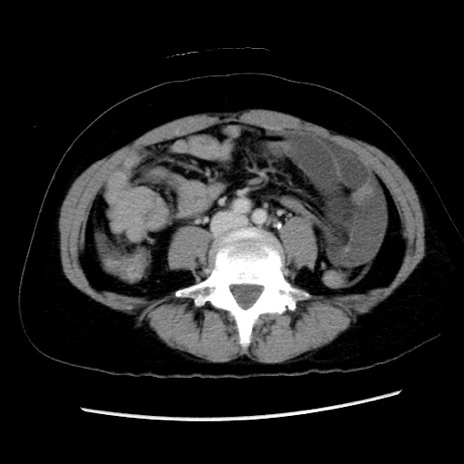

症例10(横断像)

【症例】 50歳代女性

【主訴】 腹痛

【現病歴】前日生レバーを食べた。今朝に排便あり。 昼前に突然発症の腹痛を生じ、当院救急外来を受診した。

【既往歴】 子宮筋腫にてで子宮全摘後

【身体所見】 意識清明、腹部:平坦、軟、下腹部やや左を中心に圧痛・反跳痛あり、筋性防御あり

【データ】WBC 7800、CRP 0.07